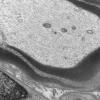

PERIPHERAL NEUROPATHY

3 NORMAL MYELIN & SCHWANN CELLS